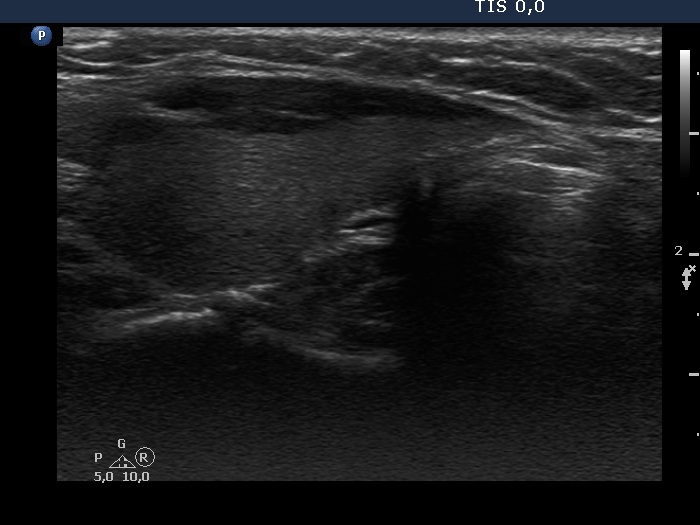

Consecutive patients with the final diagnosis of Hashimoto's thyroiditis - case 8 (659) (ultrasonographic picture 5)

Left lobe, longitudinal scan.